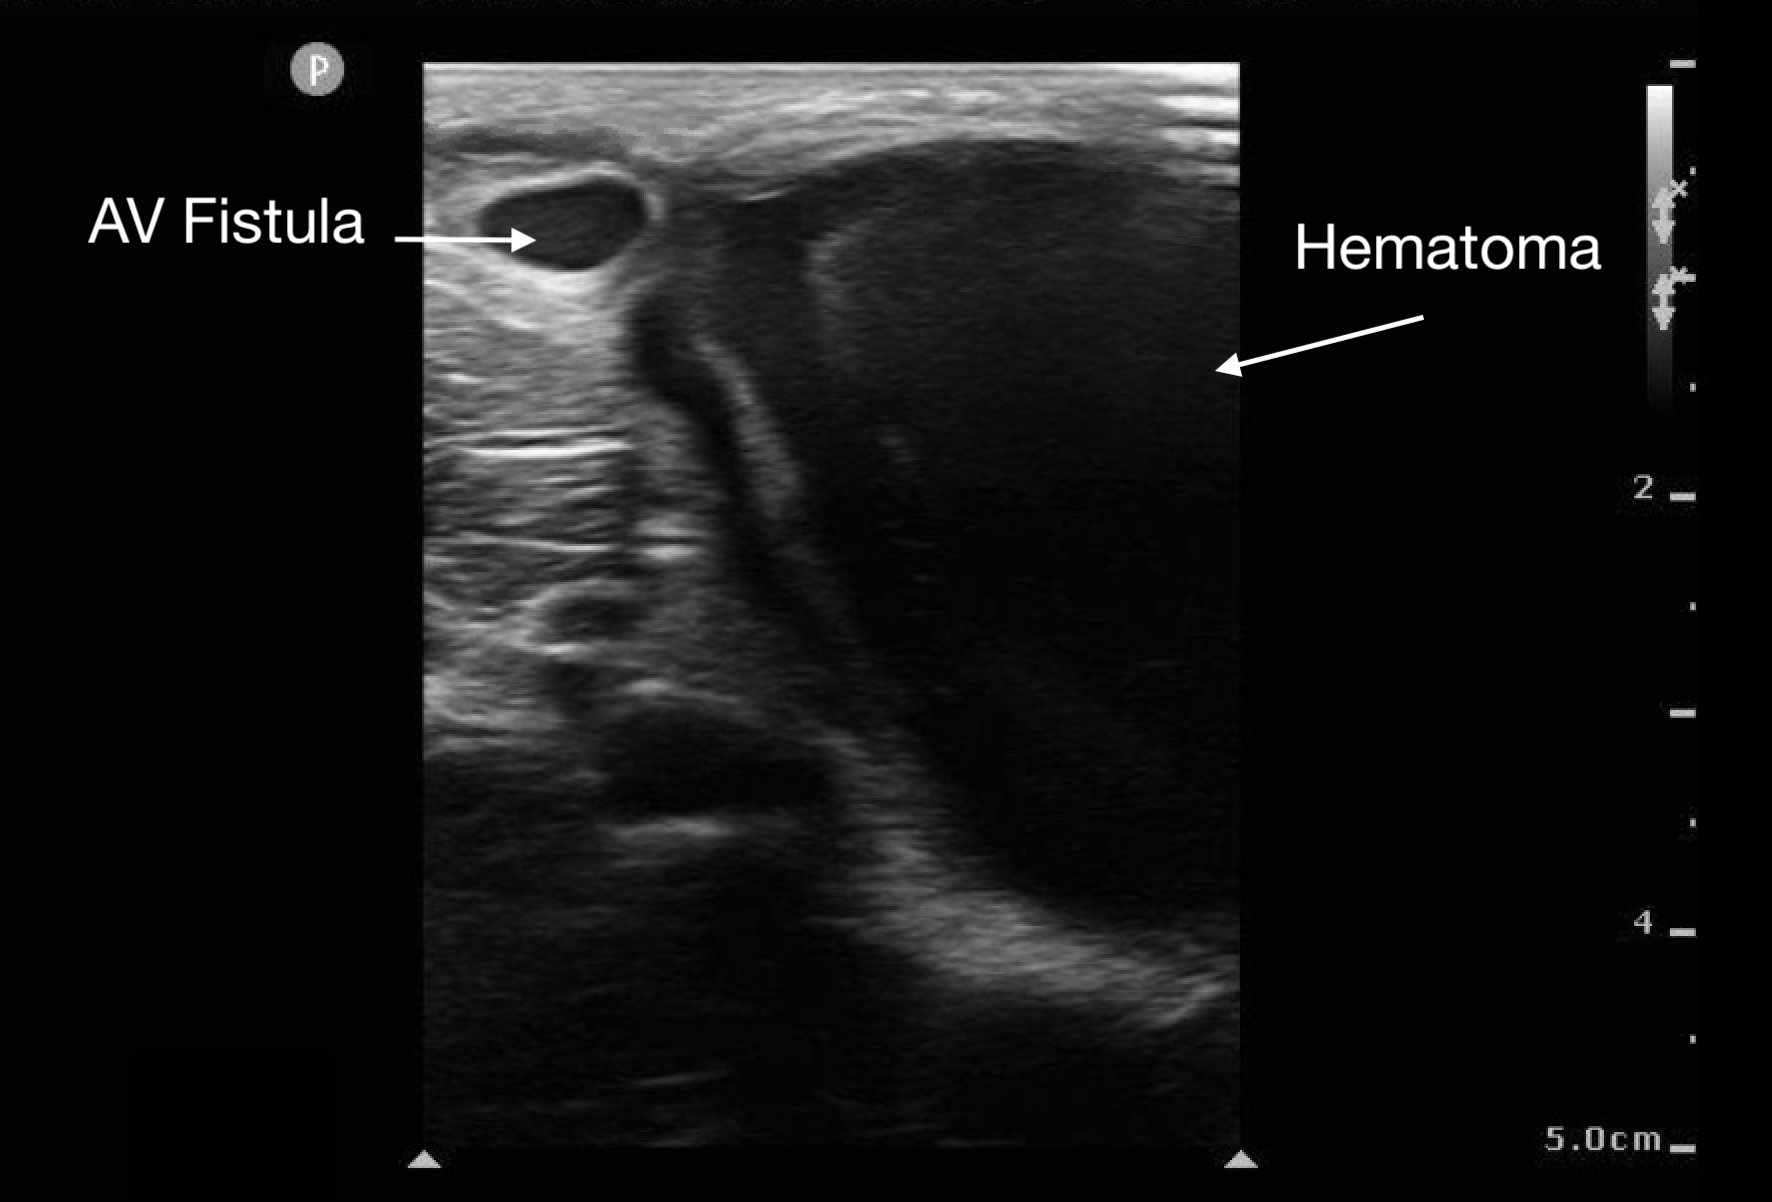

Abscesses and hematomas are readily identifiable on ultrasound as abnormal fluid collections in areas of tenderness or swelling. The appearance of the fluid varies depending on its contents, the presence of gas, and the clotting state of the hematoma. Fluid may appear anechoic (most common), heterogeneous, or even isoechoic. A key indicator in uncertain cases is the posterior acoustic enhancement generated by the fluid contents.

Figure 11.

Large hematoma from ruptured AV fistula seen in upper left corner of image.

Before draining an abscess, it is crucial to use color Doppler to rule out a pseudoaneurysm or nearby large vessels. This step helps prevent inadvertent incision into a vascular soft tissue structure, such as a lymph node, which may appear similar to an abscess.